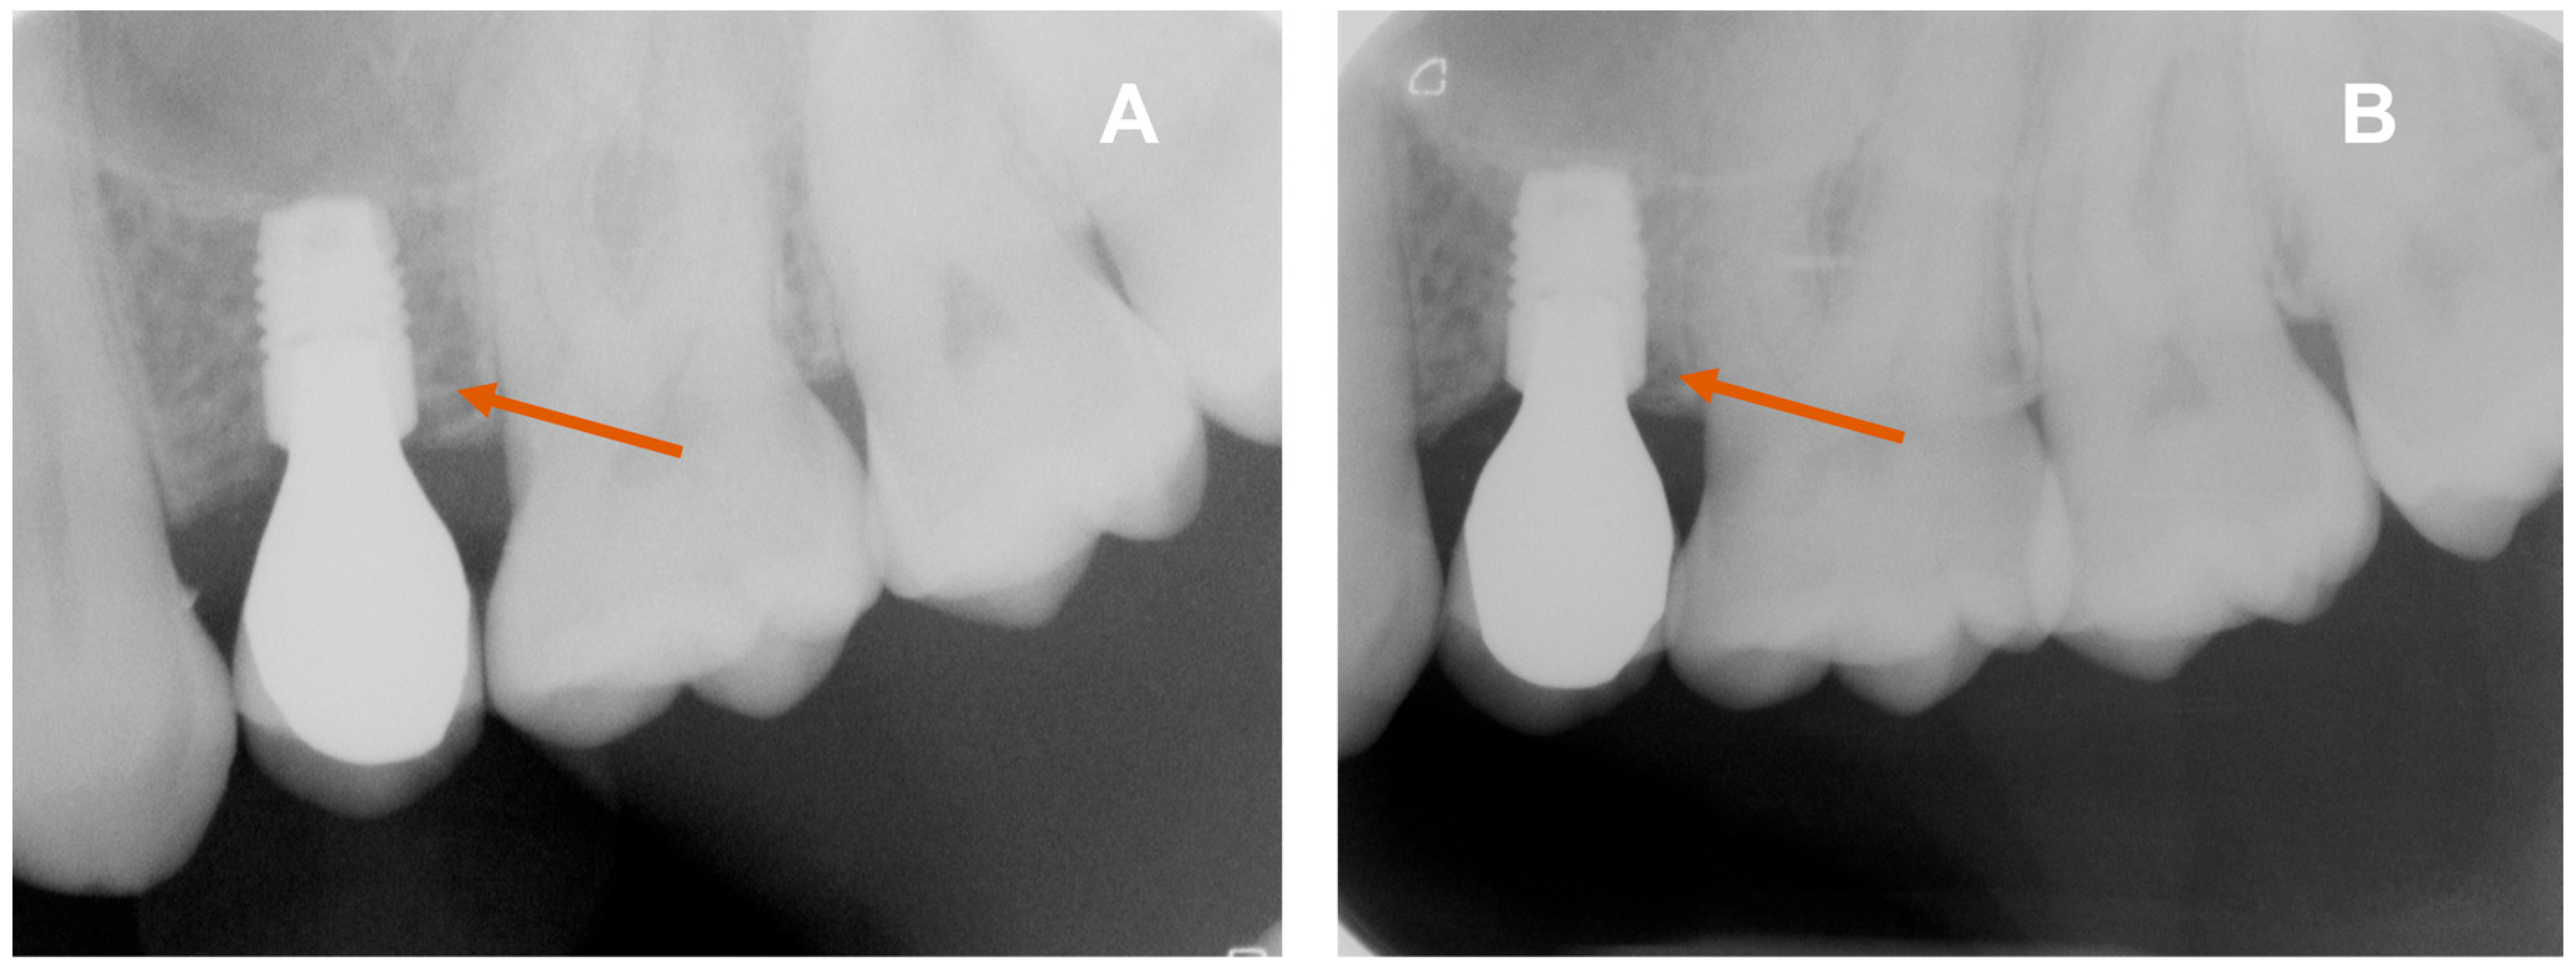

Figure 2 shows X-ray images of short implants in region 26 after prosthetic insertion (A) and 3 years after prosthetic restoration (B). The short implant in region 26 eliminated the need for augmentation (Figure 2).

Figure 2. X-ray images of short implants in region 24 after prosthetic insertion (A) and 1 year after prosthetic restoration (B). Orange arrows mark the implant with adapted peri-implant bone.